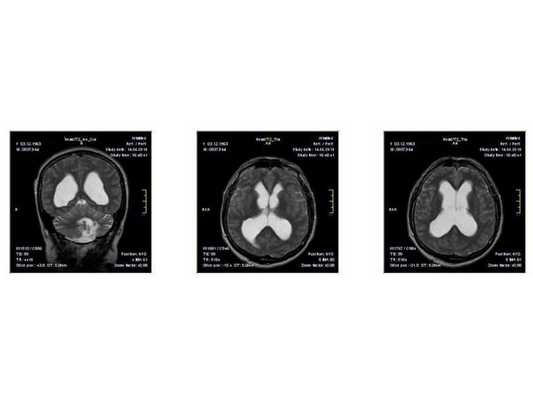

МР-томограмма нормального головного мозга. Серым цветом изображено вещество мозга, белым - ликвор. Нормальная величина жидкостных пространств головного мозга (они щелевидны). Желудочки видны внутри мозга. Субарахноидальные пространства - белая кайма вокруг мозга.

МР-томограммы при внутричерепной гипертензии и гидроцефалии. Результат недостаточного лечения повышенного внутричерепного давления. Видно избыточное скопление ликвора внутри головного мозга (в виде бабочки) и снаружи мозга (широкая белая кайма). Объем мозгового вещества уменьшен - атрофия головного мозга от давления жидкостью.

- МРТ в динамике показывает постепенное сужение желудочковой системы на 2 мм. Для сравнения представлены снимки МРТ от 14.05.2013 и от 16.10.2014.